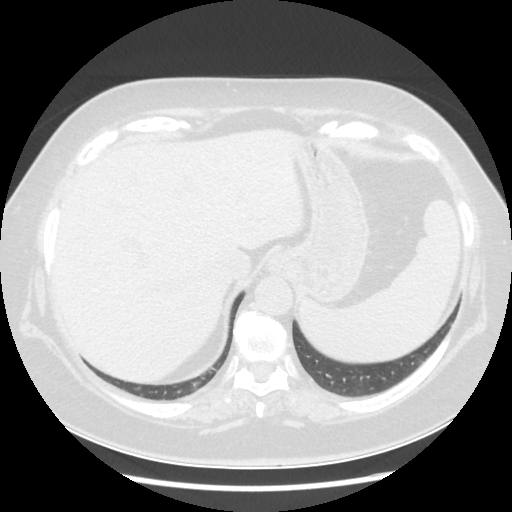

Original NATIVE CT scan (input)

Full window (WL 1023.5, WW 4095 β†’ Low βˆ’1024, High +3071)

Original VENOUS CT scan